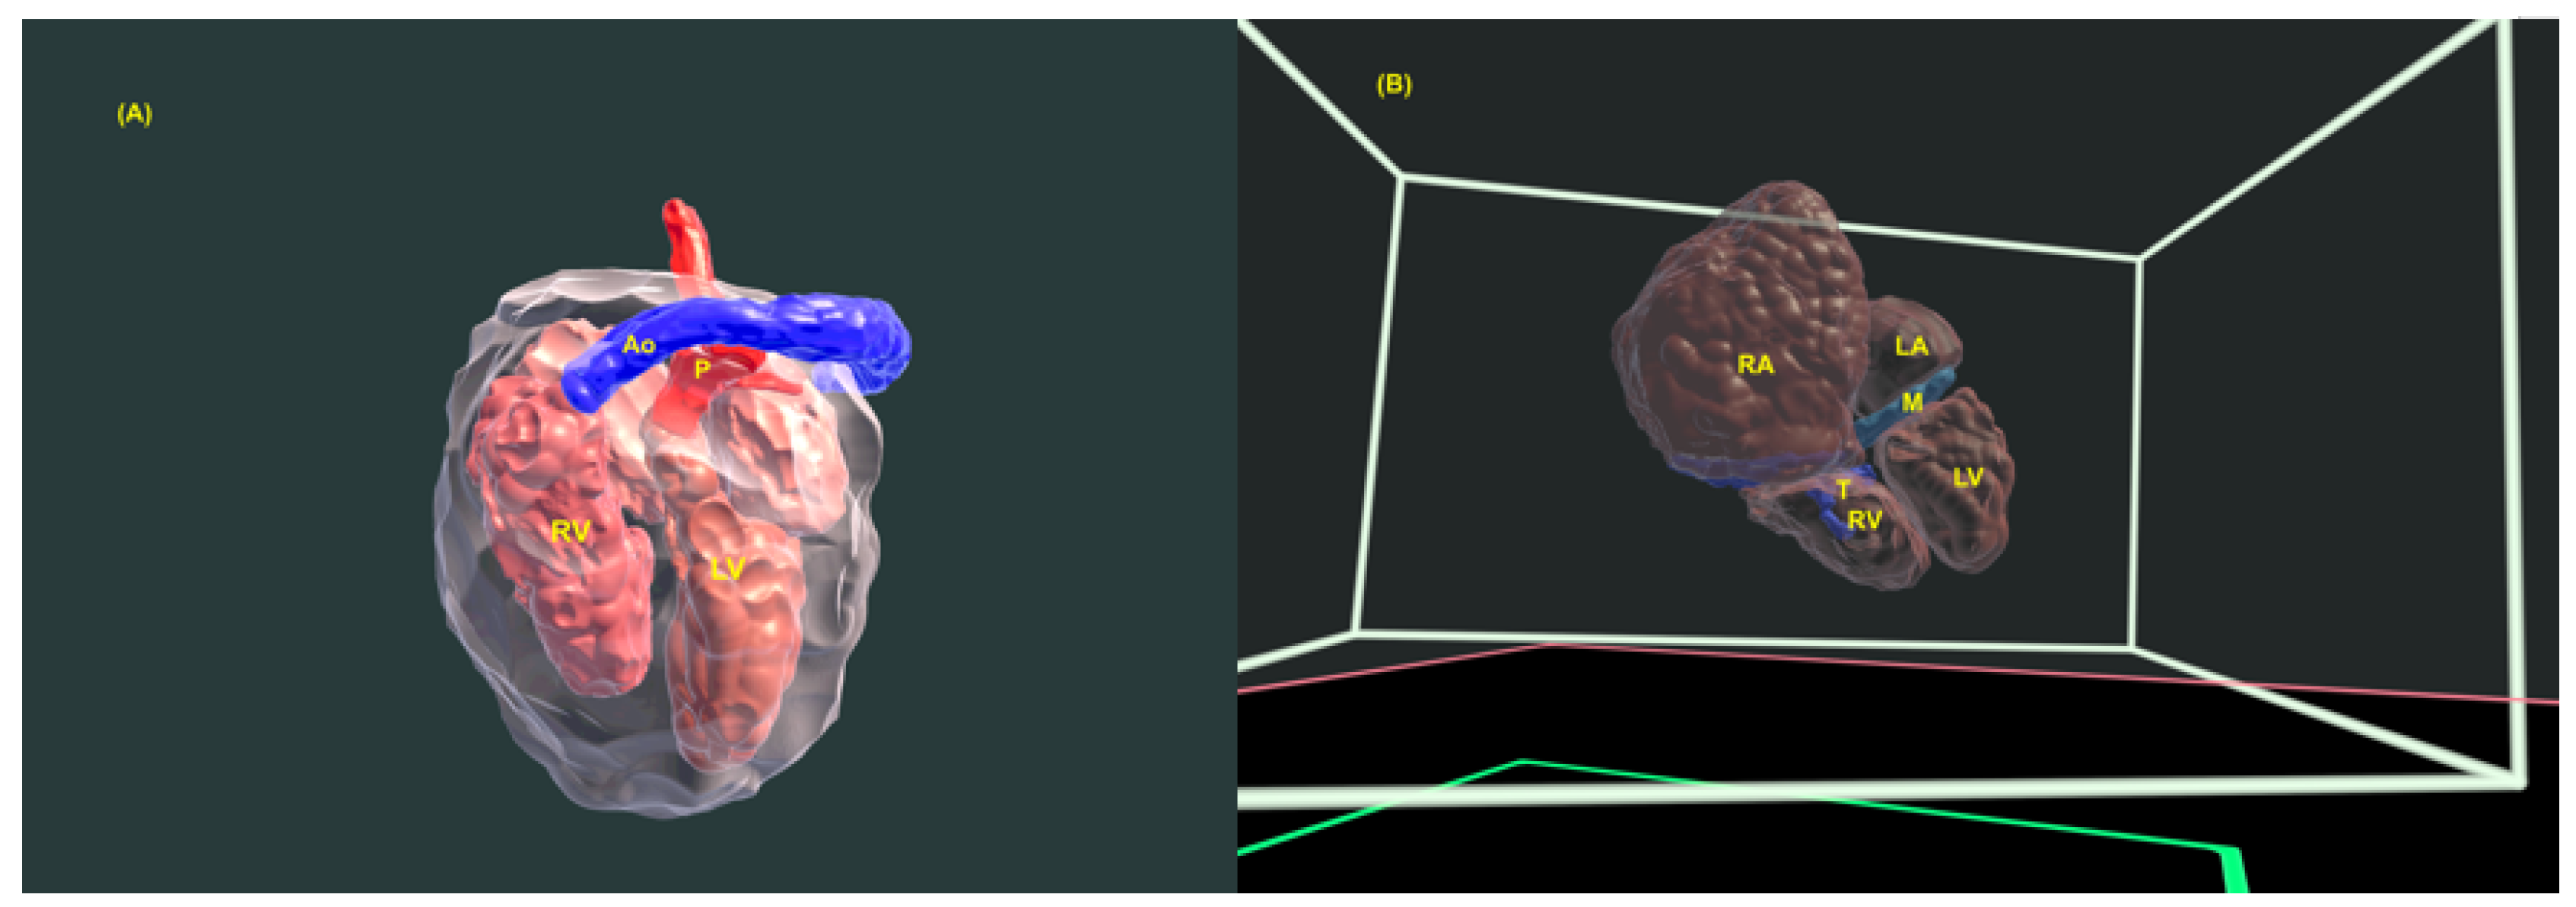

- Werner H, Lopes J, Ribeiro G, Raposo AB, Trajano E, Araujo Júnior E. Three-dimensional virtual traveling navigation and three-dimensional printing models of a normal fetal heart using ultrasonography data. Prenat Diagn. 2019, 39, 175–177.

- Bravo-Valenzuela NJ, Monteiro Pereira Leite MF, Lopes J, Arcoverde V, Ribeiro G, Araujo Júnior E; et al. Three-dimensional navigation inside a normal fetal heart in a virtual reality environment. J Clin Ultrasound. 2024 Aug 21. [CrossRef]

- Giffoni MC, Lopes J, Ribeiro G, Araujo Júnior E, Werner H. Fetal heart segmentation in a virtual reality environment. Int J Cardiovasc Imaging. 2024 Jun 4. [CrossRef]

- Nieblas CO, Bravo-Valenzuela NJ, Araujo Júnior E, Werner H. Fetal transposition of the great arteries: 3D virtual and physical models from ultrasound datasets. Int J Cardiovasc Imaging. 2024, 40, 1157–1158.

- Pires GDV, Nieblas CO, Bravo-Valenzuela NJ, Araujo Júnior E, Castro PT, Werner H. Ebstein anomaly: 3D virtual and physical models from obstetrical ultrasound data. Echocardiography. 2024, 41, e15806.

- Werner H, Ribeiro G, Arcoverde V, Lopes J, Velho L. The use of metaverse in fetal medicine and gynecology. Eur J Radiol. 2022, 150, 110241.